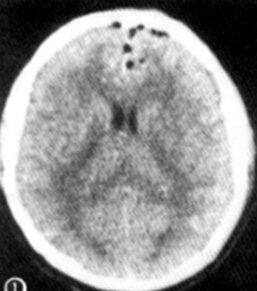

(2)张力性气颅;大量对称或非对称空气聚集,占据颅腔空间, 产生张力,压迫并刺激脑组织使其移位,而致使神经功能障碍,除头痛外,尚有进行性颅内压增高症状,严重者可危及生命。额部出现张力性气颅压迫使一侧脑组织向后移位,在CT影像上由低密度气体与脑组织形成“山峰征”。

出现此征可提示发生张力性气颅;如果骨折片刺破脑膜,蛛网膜裂孔较大,脑脊液漏出较多,造成颅内负压, 可使大量空气进入颅腔,在 CT 影像上呈脑内分散着大量弥漫性不均匀小空气泡, 形成“气泡征”,出现此征提示张力性气颅已广泛形成, 并有颅内压增高 。